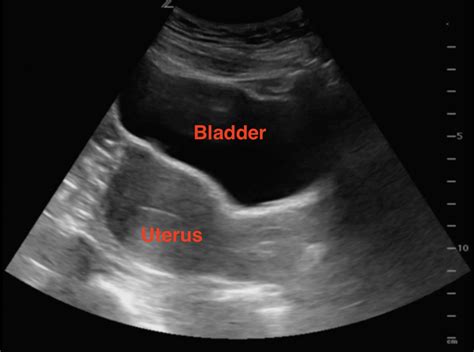

This is the most common type where the technician applies gel to your abdomen and moves a transducer over it. It is generally comfortable and non-invasive. Because sound waves travel best through liquid, it is often recommended that you arrive with a full bladder to help provide a clear acoustic window to the uterus.

If you are very early in your pregnancy (usually before 8 weeks), a transabdominal scan might not show enough detail because the uterus is still hidden behind the pubic bone. A transvaginal ultrasound uses a slim, wand-like transducer inserted into the vagina. While it may sound intimidating, it is a standard procedure that provides a much clearer, closer view of the embryo.